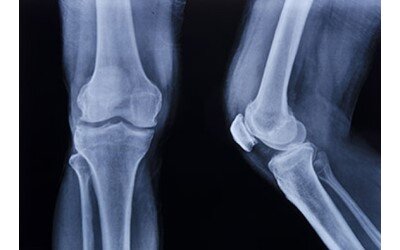

بهبود آسیب استخوانی با استفاده از داربست سه بعدی حاوی سلولهای بنیادی

آسیب های استخوانی در نواحی مختلف بدن به دنبال سوانح، تصادفات و یا بعد از جراحی های وسیع، یکی از مشکلات پزشکی روز دنیا است. معمولا برای درمان از پیوند استخوان از خود فرد یا فرد دیگر (جسد) استفاده می گردد که مشکلات و محدودیتهایی دارد. علم مهندسی بافت با استفاده از ترکیب داربست، سلول و مولکولهای زیستی فعال که اشاره شد می تواند به درمان این موارد کمک کرد.

در این مطالعه از داربستی از جنس پلی لاکتیک اسید که با دستگاه پرینتر سه بعدی ساخته شده استفاده شد که حاوی سلولهای بنیادی مغز استخوان بود. بعد از ایجاد ضایعه استخوانی در جمجمه موشهای صحرایی، حیوانات به سه گروه تقسیم شدند. یک گروه بعنوان کنترل درمانی دریافت نکردند، یک گروه با داربست به تنهایی و یک گروه با داربست حاوی سلولهای بنیادی درمان شدند. بعد از گذشت ۸ و ۱۲ هفته روند درمان پیگیری و نمونه های ناحیه آسیب از نظر بافت شناسی بررسی شد.

نتایج این مطالعه نشان داد داربست به تنهایی و داربست حاوی سلول باعث تحریک ساخت استخوان جدید شدند و حضور سلولهای بنیادی باعث افزایش کارایی داربست در ترمیم استخوان گردید. در ضمن این داربست سمیت کبدی برای حیوان ایجاد نکرد.